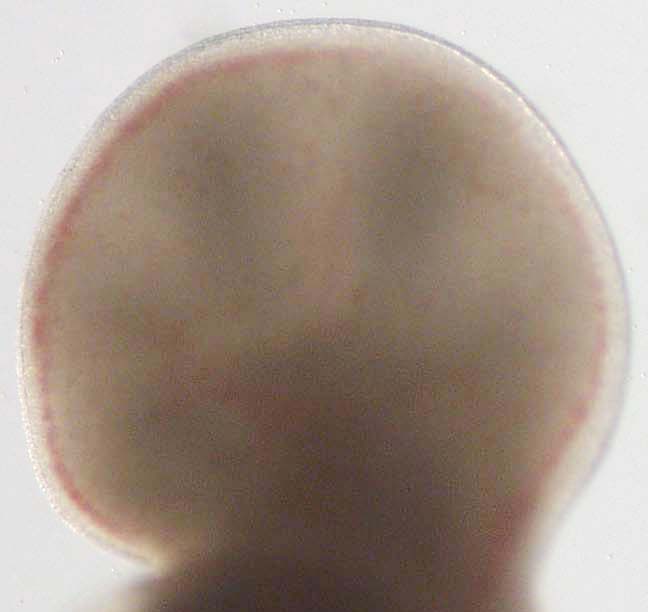

Forelimb

Stage:

CfS 17

Day:

d30-31